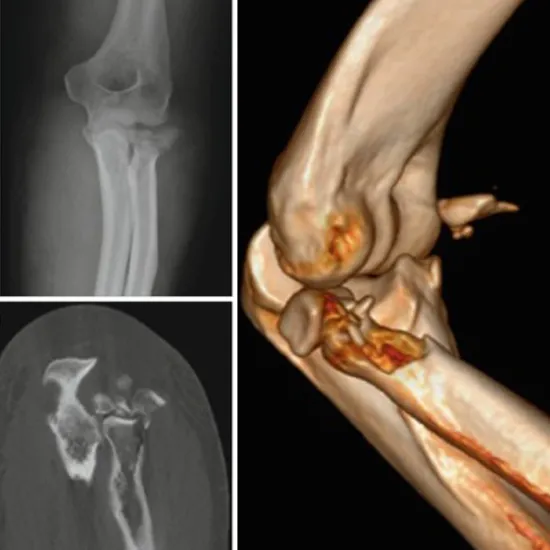

3D CT Left Elbow is a non-invasive imaging scan to visualise the bony assessment of the left elbow with 3D construction. The 3D CT elbow procedure creates detailed images with 3D construction, which helps to diagnose the abnormalities easily and early.

You need to lie on his/her back on the CT table and the left elbow is placed in the centre of the gantry and is extended palm facing upward the opposite arm is placed on the side and after proper positioning of the elbow scan is performed and the image is reconstructed in 3D to detect the problem.